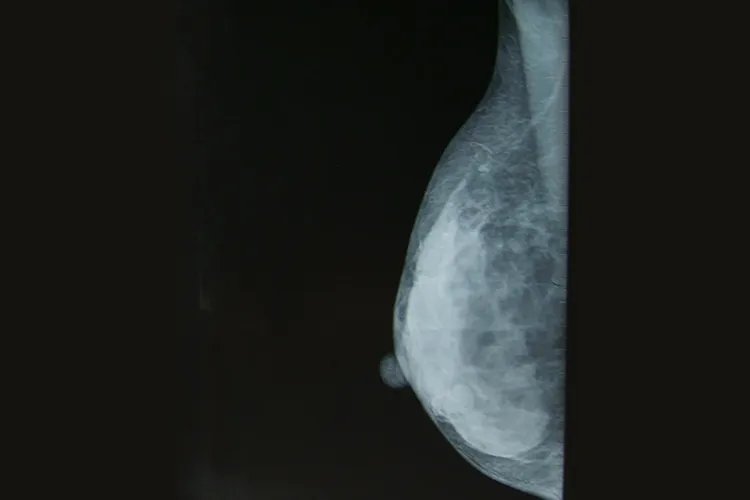

的有关信息介绍如下:概述乳腺胸片应指乳腺X线检查,可显示密度较高的乳头、乳晕,以及呈片状致密影的腺体组织等,可用于乳腺疾病的诊断和筛查。正常影像胸片是指胸部的X线,并非对乳腺组织的专一检查。乳腺胸片应指乳腺X线检查,影像可显示呈密度较高的类圆形影的乳头,一般两侧对称,位于锥形乳腺的顶端和乳晕的中央。乳晕呈盘状高密度影,位于乳头四周。乳腺的皮肤呈略高密度线样影,光滑整齐。皮下脂肪层呈低密度透亮带,位于皮肤下方。

X线上的乳腺腺体结构呈片状致密影,边缘多较模糊,由许多小叶及其周纤维组织间质融合而成。X线片上多能显示大乳导管,表现为均匀线样影,呈放射状,自乳头向乳腺深部走行。意义乳腺X线摄影是常规的乳腺疾病影像学检查方法之一,在乳腺癌早期发现、早期诊断方面发挥着重要作用,被广泛应用于乳腺疾病的诊断和乳腺癌的筛查。除X线检查外,临床常用的乳腺影像学检查还包括超声、MRI和CT等。